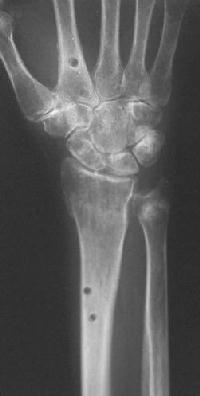

Clinical Example: Distraction plate fixation distal radius fracture

distal radius fracture